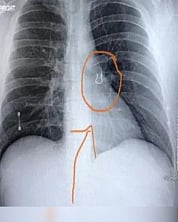

அங்கு அவருக்கு பரிசோதனை செய்யப்பட்டதில், முதலில் அவருக்கு நிமோனியா இருக்கலாம் என மருத்துவர்கள் சந்தேகித்துள்ளனர். பின்னர் எக்ஸ்-ரே எடுக்கலாம் என முடிவு செய்த மருத்துவர்கள் அதன் முடிவை பார்த்தபோது அதிர்ச்சி அடைந்துள்ளனர்.

அவரின் நுரையீரலில் வளைவாக ஏதோ ஒரு பொருள் இருந்துள்ளது. பின்னர் அறுவை சிகிச்சை மூலம் அந்த பொருள் அகற்றப்பட்டபோது, அது மூக்கு வளையம் (மூக்குத்தி) என்பது தெரியவந்தது. இது தொடர்பாக ஜோயி லிகின்ஸிடம் கேள்வி எழுப்பியபோது, 5 வருடத்துக்கு முன் தான் தொலைத்த மூக்கு வளையம் என்பதை கூறியுள்ளார்.

ஜோயி லிகின்ஸ் இரவு தூங்கும் போது முக்கில் போட்டு இருந்த வளையம் காணாமல் போயுள்ளது. முதலில் அதை தேடிய அவர் பின்னர் அதனை அப்படியே விட்டுள்ளார். இந்த நிலையில் தற்போது அந்த வளையம் வாய்வழியாக அவரின் உடலில் சென்றுள்ளது. வளையம் அவரின் நுரையீரலைக் கிழிக்காமல் வெளிப்புறமாக இருந்ததால் அவருக்கு எந்த பாதிப்பும் ஏற்படவில்லை என மருத்துவர்கள் கூறியுள்ளனர்.